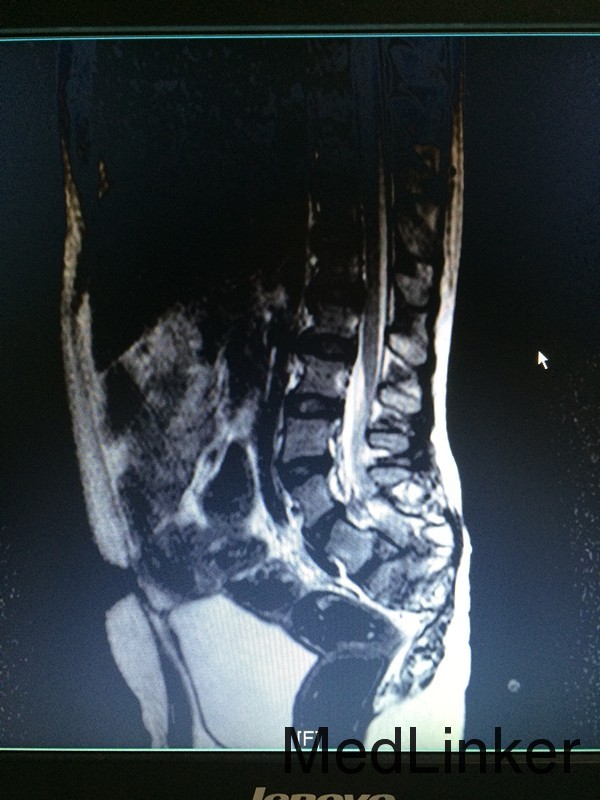

主诉:行走不稳10余年 病史:患者12岁男性,出生后即发现骶尾部包块,行走不稳,间有小便失禁,大便正常,未予特殊处理。近期患者出现行走不稳较前加重,遂来我院就诊,拟议“脊髓栓系综合征”收入院

查体:腰椎后突畸形,双小腿肌肉萎缩,双足内翻畸形,双侧踇指伸指无力。 辅助检查:行脊椎MR检查提示:骶椎发育畸形,脊髓圆锥低位,考虑脊髓栓系综合症,神经源性膀胱。

诊断:脊髓栓系综合症 治疗:神经外科联合骨科在全麻下行脊髓栓系松解、椎板修补术,术后予对症支持治疗。